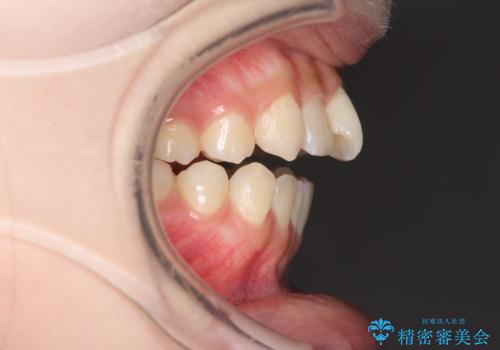

- 前歯のオープンバイトを気にして来院された患者様です。

上下前歯の前後位置が大きくずれていたため、上顎左右第一小臼歯2本を抜歯してワイヤー装置による矯正治療を行うこととしました。

オープンバイトの原因は舌の突出癖であり、癖が改善されないと治療経過に影響を及ぼすため、舌のトレーニングを指示しました。

なかなか癖が改善されず、トレーニングも断続的に行ったため、治療期間は長期化しました。